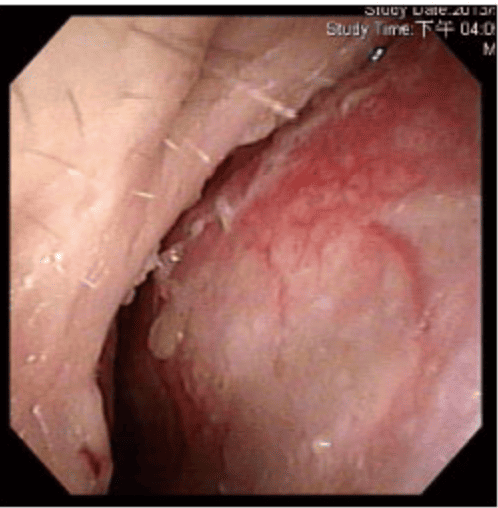

透過內視鏡檢查時,發現F先生右側尾端鼻中隔彎曲,幾乎貼近側壁,而且右側鼻阻力圖呈水平,代表F先生右側鼻空肌膚不能呼吸。鼻中隔軟骨扭曲變形、左上側軟骨凹陷萎縮,我們團隊先進行鼻部結構拆解及鼻中隔成形手術,再利用取下的鼻中隔軟骨進行重建,同時進行右側截骨術(Osteotomy),從根本矯正歪斜的鼻樑。